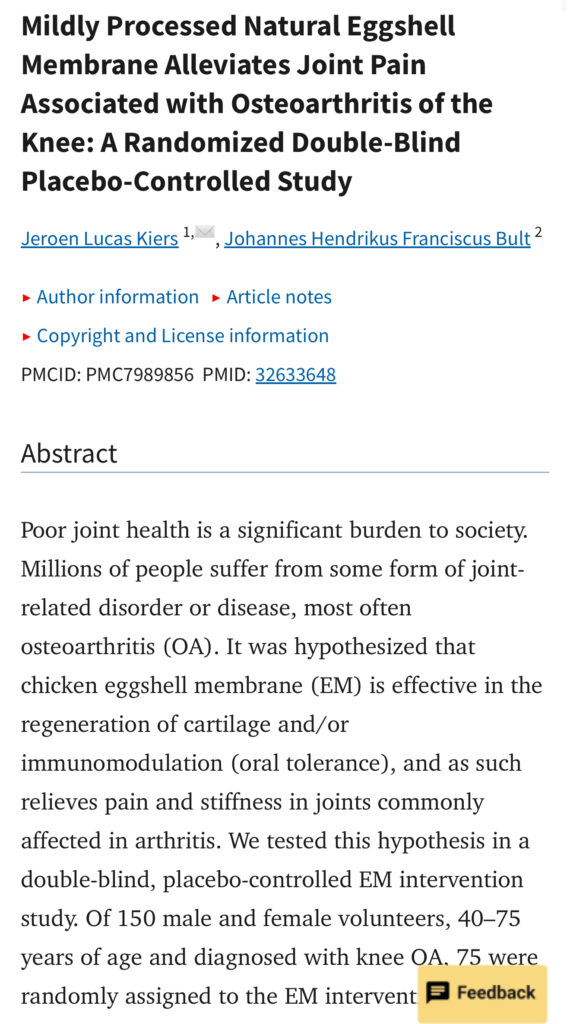

A premium natural extract from eggshell membrane developed in Spain. Contains over 500 active compounds, including collagen, hyaluronic acid, glucosamine, and chondroitin.

- Reduces joint inflammation naturally

- Rebuild, replanish damaged cartilage & Fluid

- Relieves knee pain in 7 days